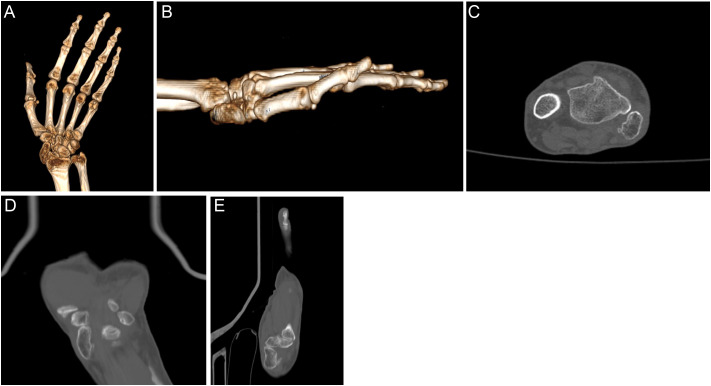

孤立性舟状骨脱位是一种极为罕见的损伤。如果不及时治疗,后果可能是灾难性的。本文报道一例被忽视的开放性舟状骨脱位损伤的晚期并发症。一名63岁妇女因左腕疼痛和活动受限的症状入院骨科门诊。她的病史显示,大约45年前,由于被困在一辆手推车和一棵树之间,她的左手腕曾有过开放性损伤。x线和计算机断层显示舟状骨掌侧脱位、月骨塌陷、晚期关节炎改变和月头关节囊性改变。决定手术治疗。左腕行舟状骨切除及放射性腕关节融合术。孤立性舟骨脱位是一种罕见的损伤。在急性期早期识别和治疗可预防严重并发症并取得成功。晚期手腕关节炎可在延迟病例中观察到。对于完全丧失运动能力的晚期病例,放射性腕关节融合术是一个成功的治疗选择。

Isolated dislocation of the scaphoid bone is an extremely rare injury. If left untreated, results may be catastrophic. This paper presents a late complication of a neglected open scaphoid dislocation injury. A 63-year-old woman was admitted to the orthopedic outpatient department with symptoms of pain and restricted movement in her left wrist. Her medical history revealed a previous open injury to her left wrist approximately 45 years ago due to being trapped between a cart and a tree. X-ray and computed tomography showed volar dislocation of the scaphoid bone, collapse of the lunate bone, advanced arthritic changes, and cystic alterations in the lunocapitate joint. The decision on surgical treatment was made. Scaphoid excision and radiometacarpal fusion surgery were performed on her left wrist. Isolated scaphoid dislocations are rare injuries. Early recognition and treatment in the acute phase prevent severe complications and yield successful results. Advanced wrist arthritis can be observed in delayed cases. Radiometacarpal fusion is a successful treatment option for advanced cases with complete loss of motion.